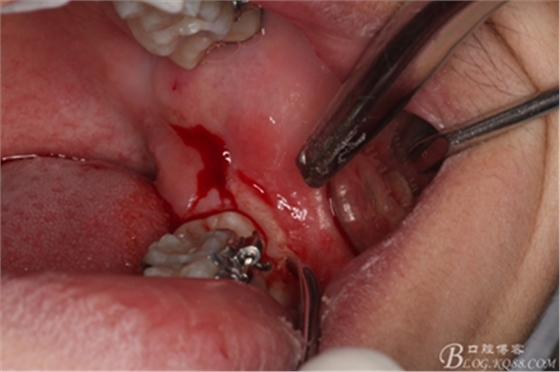

圖5.行遠(yuǎn)中水平切口+37近中垂直切口

圖6.兩個(gè)切口的交界處翻瓣